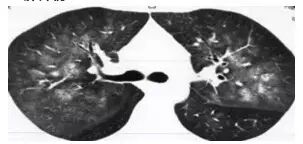

1. 肺泡蛋白沉积症

患者的肺像铺路石一样